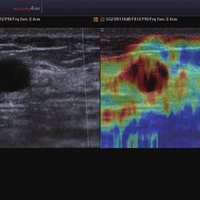

• ElastoScan™ ermöglicht eine genauere Visualisierung von Tumoren und erfasst und dokumentiert Gewebesteifheiten.

Das Ultraschallsystem hebt sich besonders durch seine 3D-Technologie wie die Face Auto Detection für detaillierte Ultraschallbilder von Föten oder das Volume Shade Imaging, das sich auf die lebensnahe Darstellung von Schattierungen und Hauttönen fokussiert, ab. Mit weiteren wertvollen Technologien wie dem ElastoScan™ werden Tumore schneller erfasst und durch die HD Volumen Bildgebung sowie das DMR+™ eine erstklassige Bildqualität erzielt.